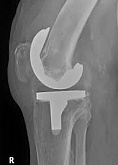

Endoprothetik des Kniegelenks

In den späten Stadien der Arthrose des Knies durch eine ausgeprägte Begrenzung der Bewegung begleitet, konstant starke Schmerzen, körperliche Unversehrtheit Verformung bis zur Genesung der einzige Weg ist der Ersatz des betroffenen Gelenks für eine künstliche - Endoprothetik.

Diese Methode ermöglicht es Ihnen, die richtige Form des Gliedes, eine vollständige Palette von Bewegung im Gelenke, zu entlasten ständige Schmerzen und Knirschen bei Bewegung und als Ergebnis wieder herzustellen, signifikant dem Patienten Lebensqualität zu verbessern.

Im Folgenden sind Röntgenaufnahmen und Fotografien, die die Strecke der Bewegung in der betroffenen Gelenke vor und nach der Operation veranschaulichen.